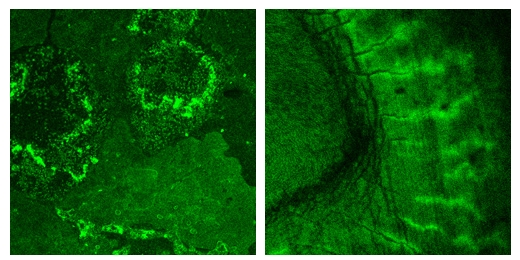

| Deposits of hydroxyapatite crystal (l.) and the same mineral in a cross section of a human tooth (r.) light up bright green where they’ve been tagged with a new peptide created at NIST to bond specifically to the compound. The peptide has been linked to a fluorescent stain for imaging.

Credit: NIST |